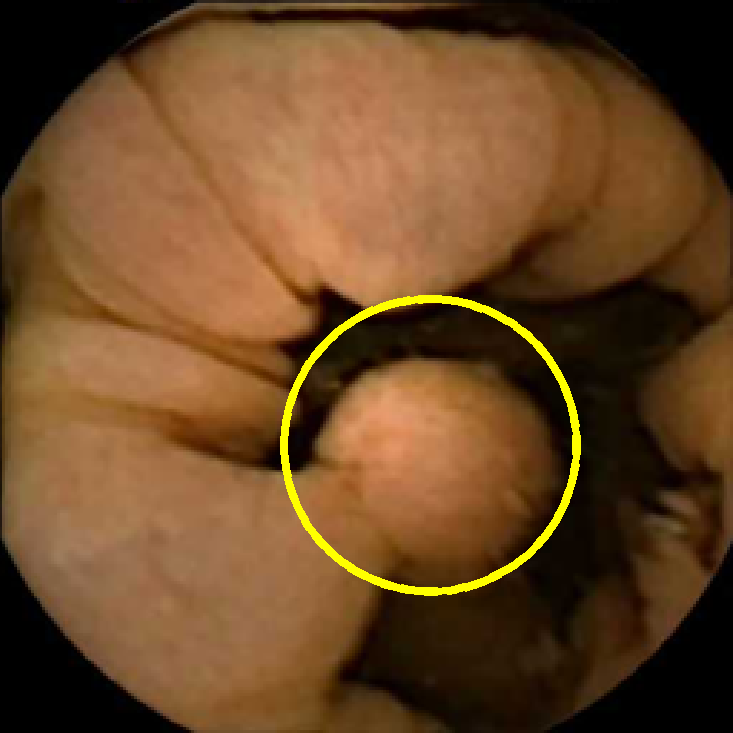

We illustrate the above considerations in Figure 4, where we compare the ellipses of inertia for a polyp frame and two frames with pronounced mucosal folds. The ellipses we plot are

| (20) |

where . The scaling term in front of is chosen so that the area of the ellipse of inertia is the same as the size of the corresponding feature.

As expected, we observe that the ellipses corresponding to mucosal folds (feature 2 in the second row and features 2 and 3 in the third row of Figure 4) are indeed much more stretched out than the ellipse corresponding to a polyp (feature 1 in the first row of Figure 4). Stretched ellipses imply higher eccentricity, thus we impose the following criterion

| (21) |

with some threshold to select moderately stretched features that are more likely to correspond to polyps.